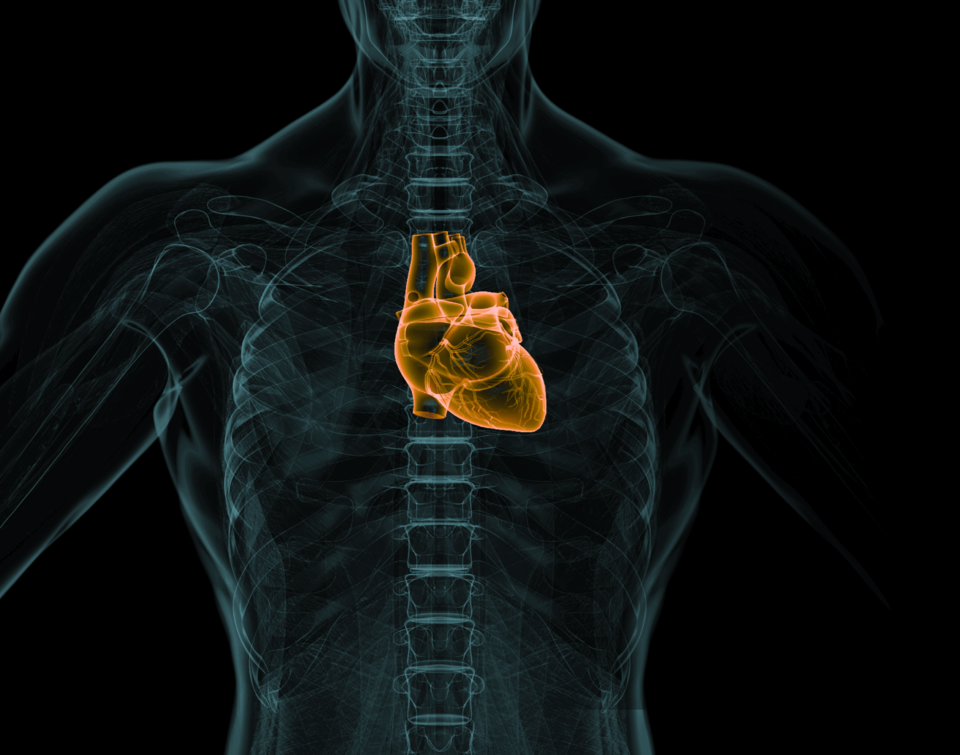

uCT 780 依托0.5mm切割的80排160层时空影像链,从数据源头提升图像质量,大幅提高早期微小病灶检出率,助力肿瘤早筛早诊;以0.3s超快转速,结合智能冠脉最佳时相算法(ePhase) ,突破高心率扫描限制,高清呈现细微结构,实现冠脉血管的精准成像。

精准心脏扫描,提升冠脉检查成功率

0.3s转速结合ePhase算法

自适应冠脉对焦,有效避免搏动伪影

0.3s机架旋转速度,大幅提高时间分辨率

心脏冠脉一键提取,高清呈现解剖结构细节